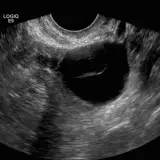

Over 2,100 interactive radiology cases, curated by radiologists for your level of training. Scroll, window, and view cases full screen — just like on PACS. Click linked findings in each writeup to jump straight to them on the image. Cases include sample reports, a focused discussion section, original illustrations, and videos.

PACSで期待されるツールを完備した完全インタラクティブな症例 — スクロール、ウィンドウ調整、ズーム、パン、計測、ROI、フルスクリーンモード。

重要な所見を症例画像上に直接ハイライトする豊富なアノテーション。症例解説内のリンクされた所見をクリックすると、スキャン上の正確な位置へジャンプできます。